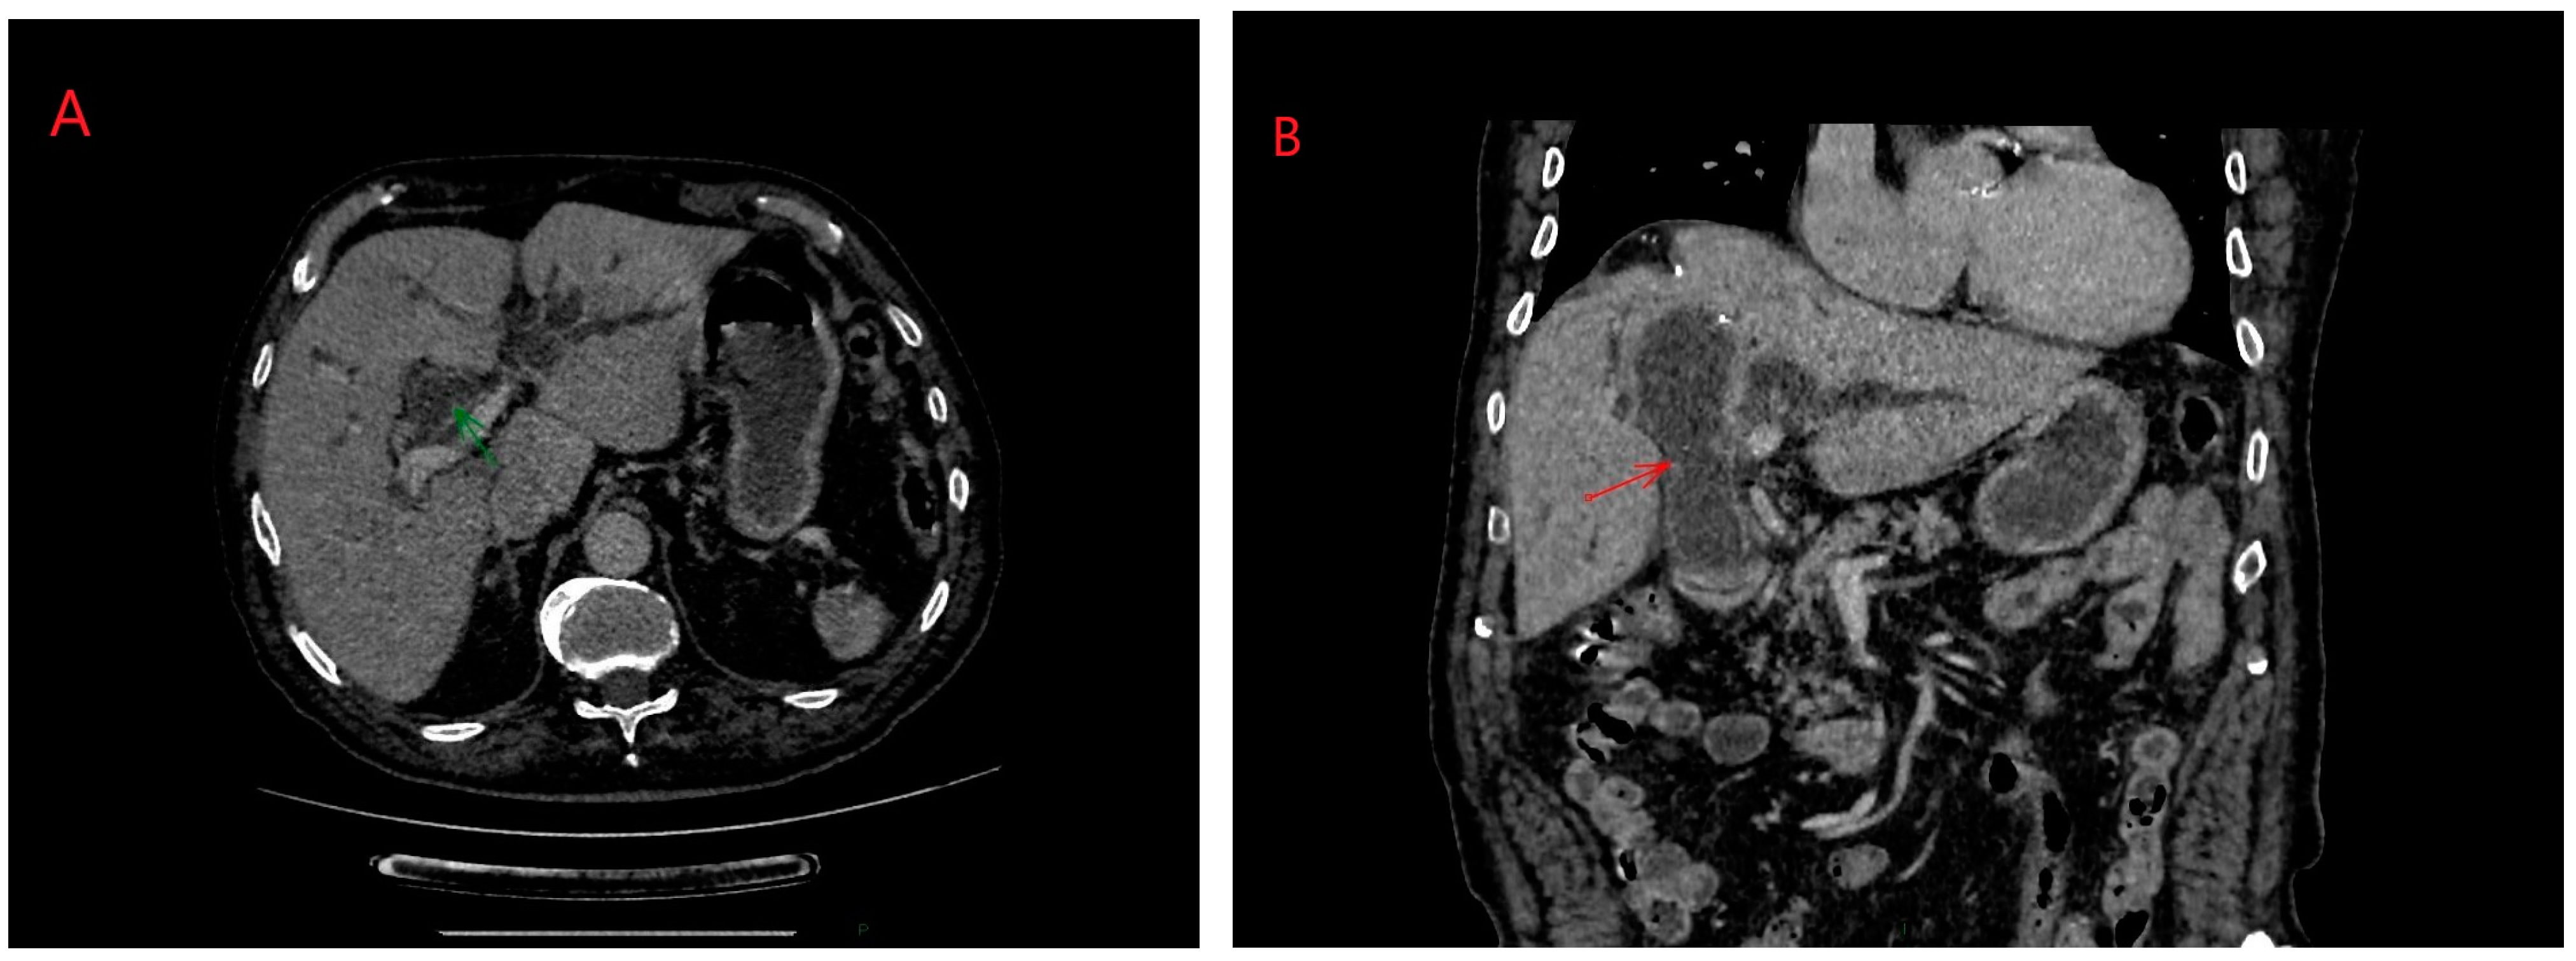

ERCP (Endoscopic Retrograde Cholangiopancreatography) in hydatid disease is indicated in cases of cyst rupture into the main bile duct, a condition that can be diagnosed via CT/MRI imaging (Figure 3 and Figure 4) [14]. Obstruction caused by daughter vesicles, remnants of the proligera membrane, inflammation resulting from subsequent cholangitis can be resolved through this approach. After identifying and cannulating the duodenal papilla, radiological examination of the bile duct was performed, followed by sphincterotomy and extraction of the hydatid contents using a Dormia probe. Identifiable lesions in the bile ducts and inflammatory strictures can be stented, and with the maneuver, along with sphincterotomy, bile duct decompression can be achieved (Figure 5).

Figure 3.

(A,B) Right lobe hydatid cyst rupture in right biliary duct: axial and coronal planes. Personal collection.